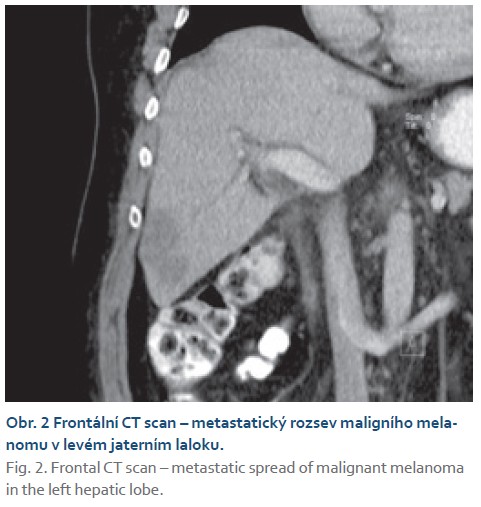

Rok po transplantaci (v únoru 2010) byl pacient hospitalizován k provedení protokolární jaterní biopsie, během níž byla na sonografii (USG) nalezena dvě ložiska v levém jaterním laloku. Bylo doplněno CT břicha (obr. 1, 2), kde byla ložiska popsána jako nejasná, se zvětšeným paketem uzlin retroaortálně, hlavním diagnostickým závěrem bylo podezření na přítomnost lymfomu. O pár dní později byl pacient přijat pro febrilie nejasné etiologie po necílené jaterní biopsii. Následně proběhla biopsie ložisek pod USG kontrolou a endosonografie, při které byla odebrána biopsie z retroaortálních lymfatických uzlin. Definitivním závěrem z histologicko-cytologického (cytoblok a cytologie) vyšetření byla přítomnost maligního melanomu. Od transplantace k diagnóze maligního melanomu uplynulo 395 dní. Pacient za hospitalizace podstoupil podrobné onkologické vyšetření (v dubnu 2010) a byla indikována terapie interferonem alfa, první aplikace proběhla bez komplikací. Během onkologické léčby byla pacientovi upravena imunosupresivní terapie (sirolimus 3 mg a mykofenolát mofetil 500 mg). V době léčby byla na USG přítomna v játrech dvě větší a řada menších ložisek (obr. 3). RTG snímek plic popisoval další suspektní ložiska v pravém horním plicním poli. Byla doplněna taktéž scintigrafie skeletu s nálezem osteolytických ložisek 8. a 9. žebra pravděpodobně metastatické etiologie.